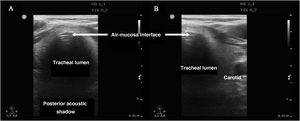

Confirmation of intubationConfirmation of correct positioning of the ETT is crucial, since it has been estimated that 3.3% of all emergent intubations place the tube in the esophagus.17

Tracheal ultrasound has been shown to be as useful as capnography in excluding esophageal intubation, with a sensitivity of 98.7% and a specificity of 97.1%, and it performs even better in patients with low cardiac output in the context of cardiac arrest.18 Furthermore, tracheal ultrasound offers the advantage of not needing the start of ventilations for confirmation (in contrast to capnography), thus reducing the risk of gastric distension and bronchoaspiration.

In order to discard esophageal intubation we need to use a high-frequency linear transducer located at the suprasternal notch, obtaining an anterior transverse image of the neck and airway. In this plane, the trachea is identifies as a hyperechogenic inverted U-shaped line generated by the mucosa-airway interface, with a typical posterior acoustic shadow artifact (Fig. 4). The esophagus is collapsed and in a left lateral paratracheal position. Esophageal intubation would be detected by the observation of an anechoic circular structure adjacent to the trachea (generally on the left side of the trachea) - a sign known as “double trachea” (Fig. 4).

A protocol has been proposed,16 combining tracheal and thoracic ultrasound, to assess the viability of ultrasound in confirming correct positioning of the ETT in ICU patients (Algorithm 1).